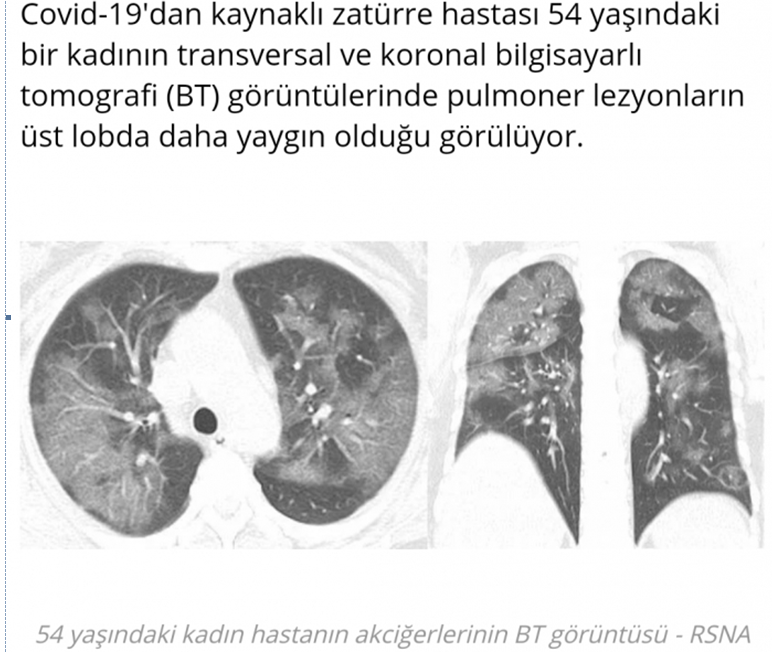

SONUÇ: Özel bir salgın döneminden geçtiğimiz şu günlerde Covid 19 hastalarının da en önemli ölüm nedeni akciğer tutulumuna bağlı zatürredir. Sigara içenler bir an önce sigarayı bıraksınlar. İyi beslenelim, evlerde kalalım.